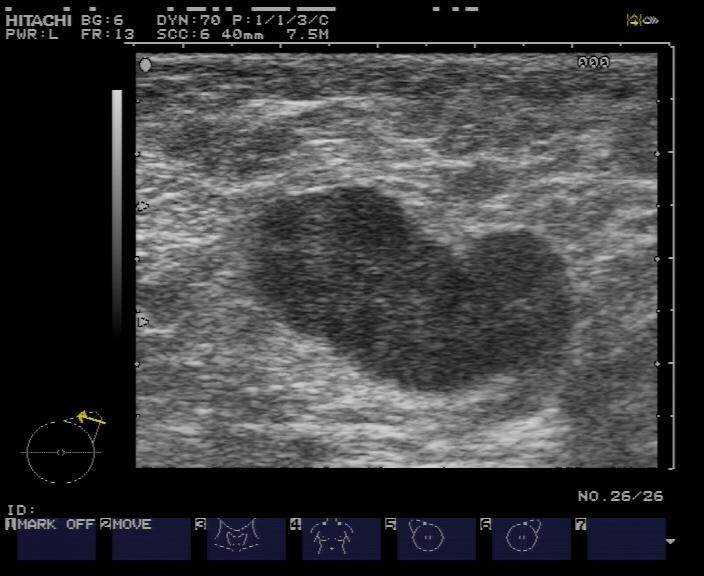

所以,第一步的“数据清洗”就成了苦活累活。好消息是,现在有了像BUSClean这样的开源工具来帮忙-7。它能像一位细心的质检员,自动识别并过滤掉那些无效的图像(比如大片黑的),把带有彩色血流标记、弹性成像等特殊模式的图像分门别类,还能智能地识别并裁剪出超声扫描的有效区域,把医生手绘的测量卡尺和文字注释提取出来-10。这就好比在把五湖四海的方言翻译成标准普通话,为后续的AI学习打下了坚实的基础。

AI病例库的发展,离不开开放和共享的精神。学术界正在贡献更多宝贵的资源,比如2025年公开的BUS-UCLM数据集,包含了38名患者的683张图像,每张图像都有专家标注的精确病灶分割区域(良性用绿色,恶性用红色),为研究者开发更精准的分割和分类模型提供了“练兵场”-3。